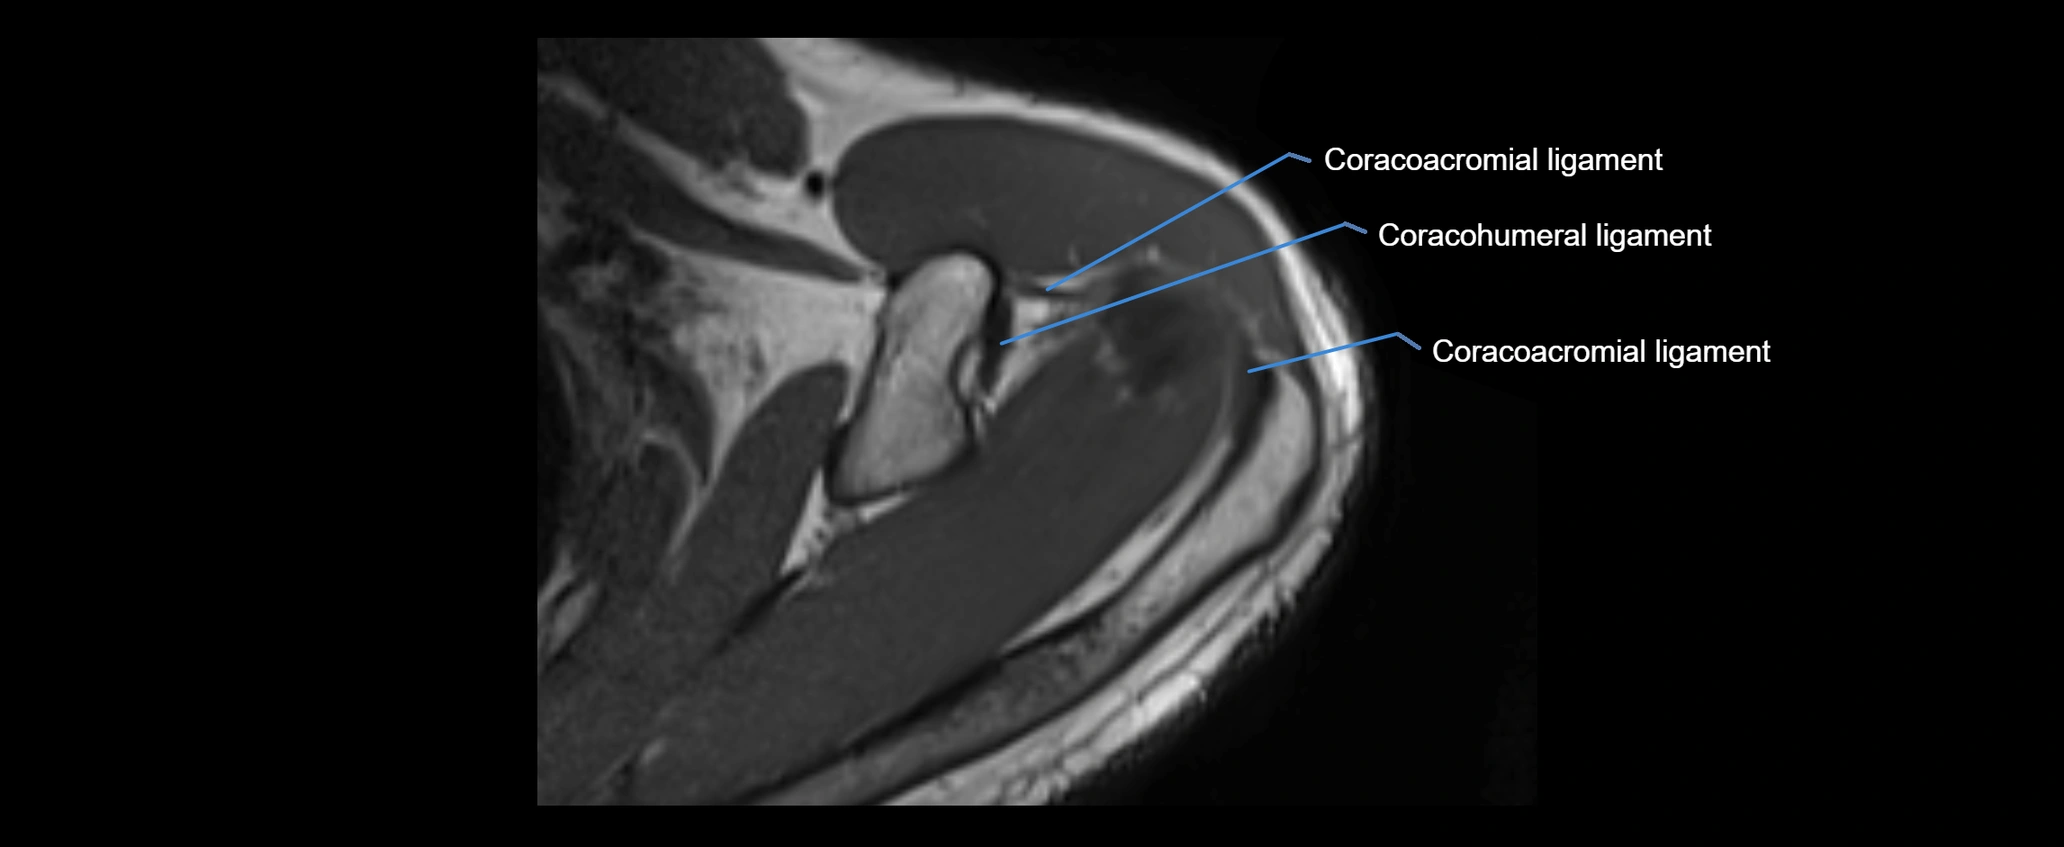

MRI images

image